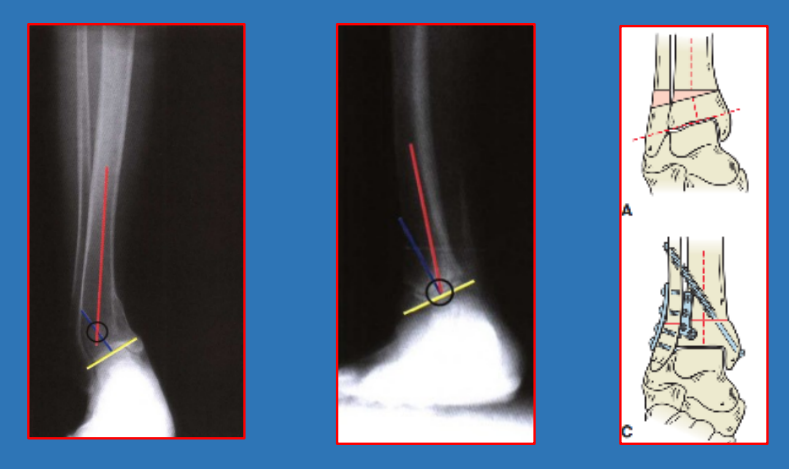

腓骨短缩测量

胫距角talocrural angle:通过在踝穴位X线片上测量内、外踝尖端连线与胫骨远端关节面平行线的夹角。正常值为8~15°,与健侧相差3°以上即表示有腓骨短缩。

胫骨远端力线异常-LDTA

胫骨远端外倾角Lateral distal tibialangle,LDTA:正位片上,胫骨远端关节面平行线与胫骨干轴线的夹角:正常86~92°,平均89°

胫骨远端力线异常—ADTA

胫骨远端前倾角Anterior distal tibialangle,ADTA:侧位片上,胫骨远端关节面平行线与胫骨干轴线的夹角正常80±2°